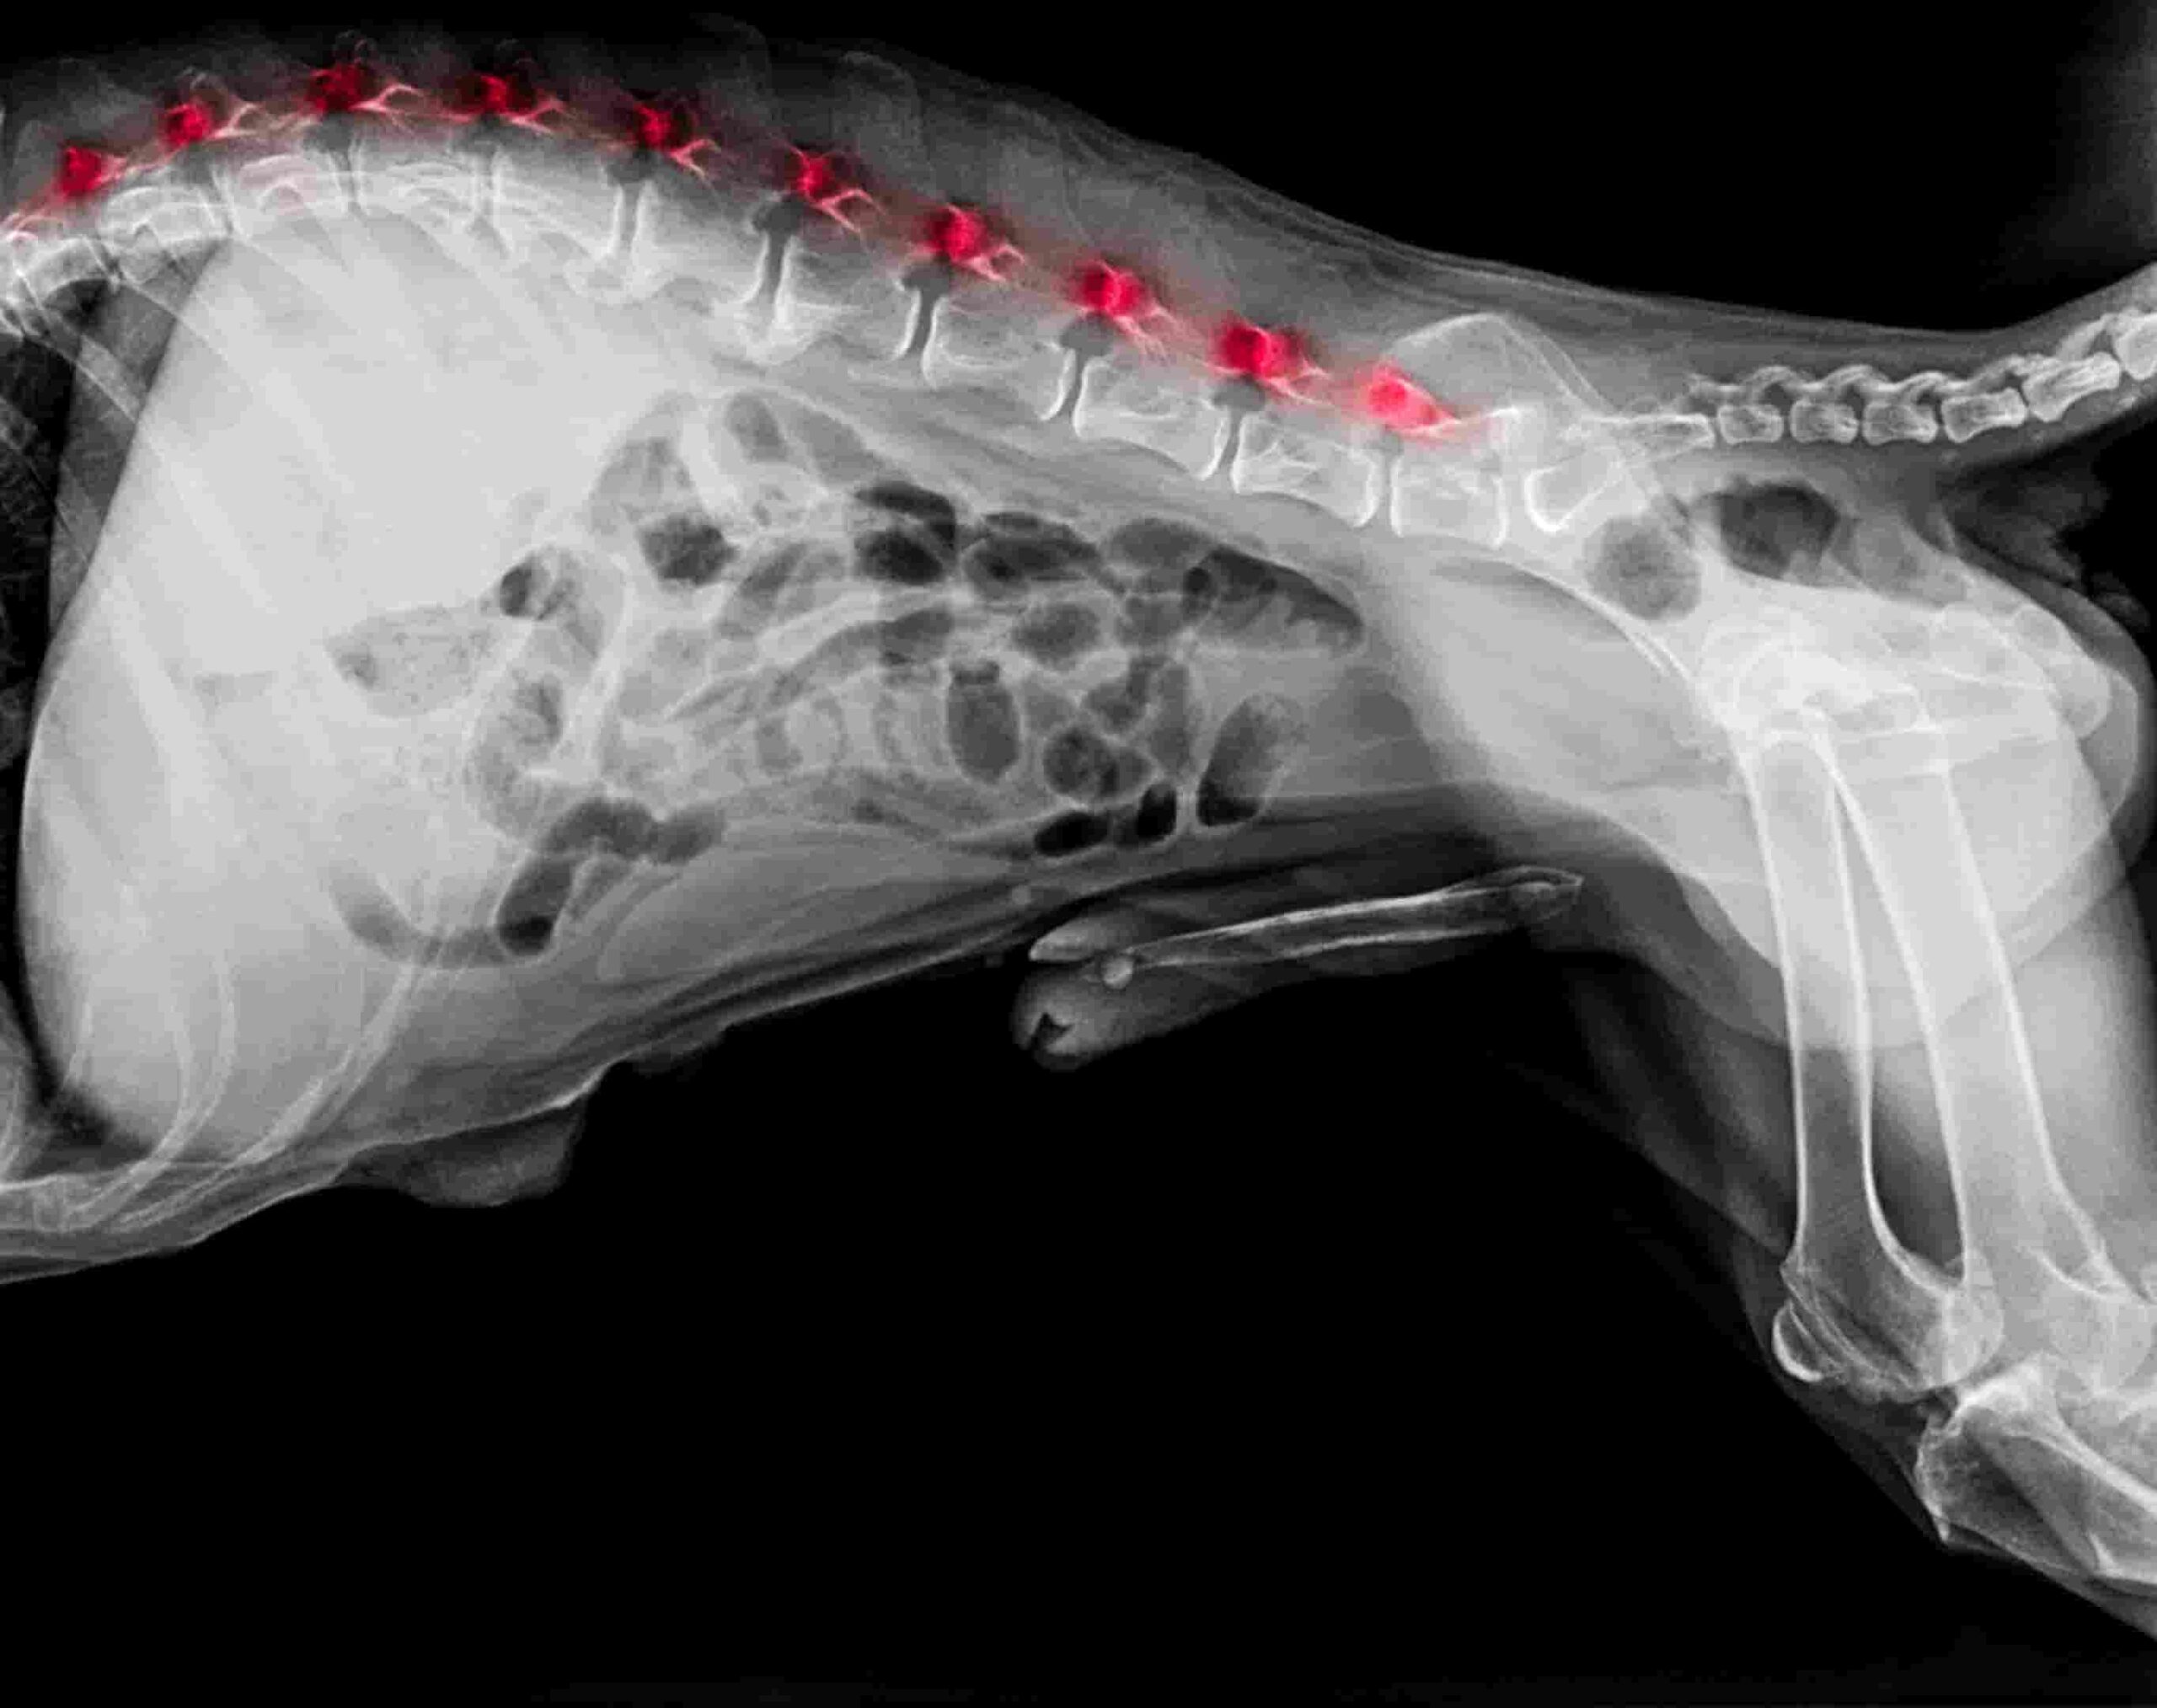

- Röntgenaufnahmen: Das Röntgenbild ist der Goldstandard bei Spondylose. Auf den Bildern sind die Veränderungen an den Wirbelkörpern meist deutlich zu erkennen. Wir sehen helle, schnabelförmige Zubildungen an der Unterseite der Wirbel, die sogenannten Spondylophyten. In weit fortgeschrittenen Fällen zeigen sich durchgehende knöcherne Brücken, welche die Wirbelzwischenräume komplett überbrücken.